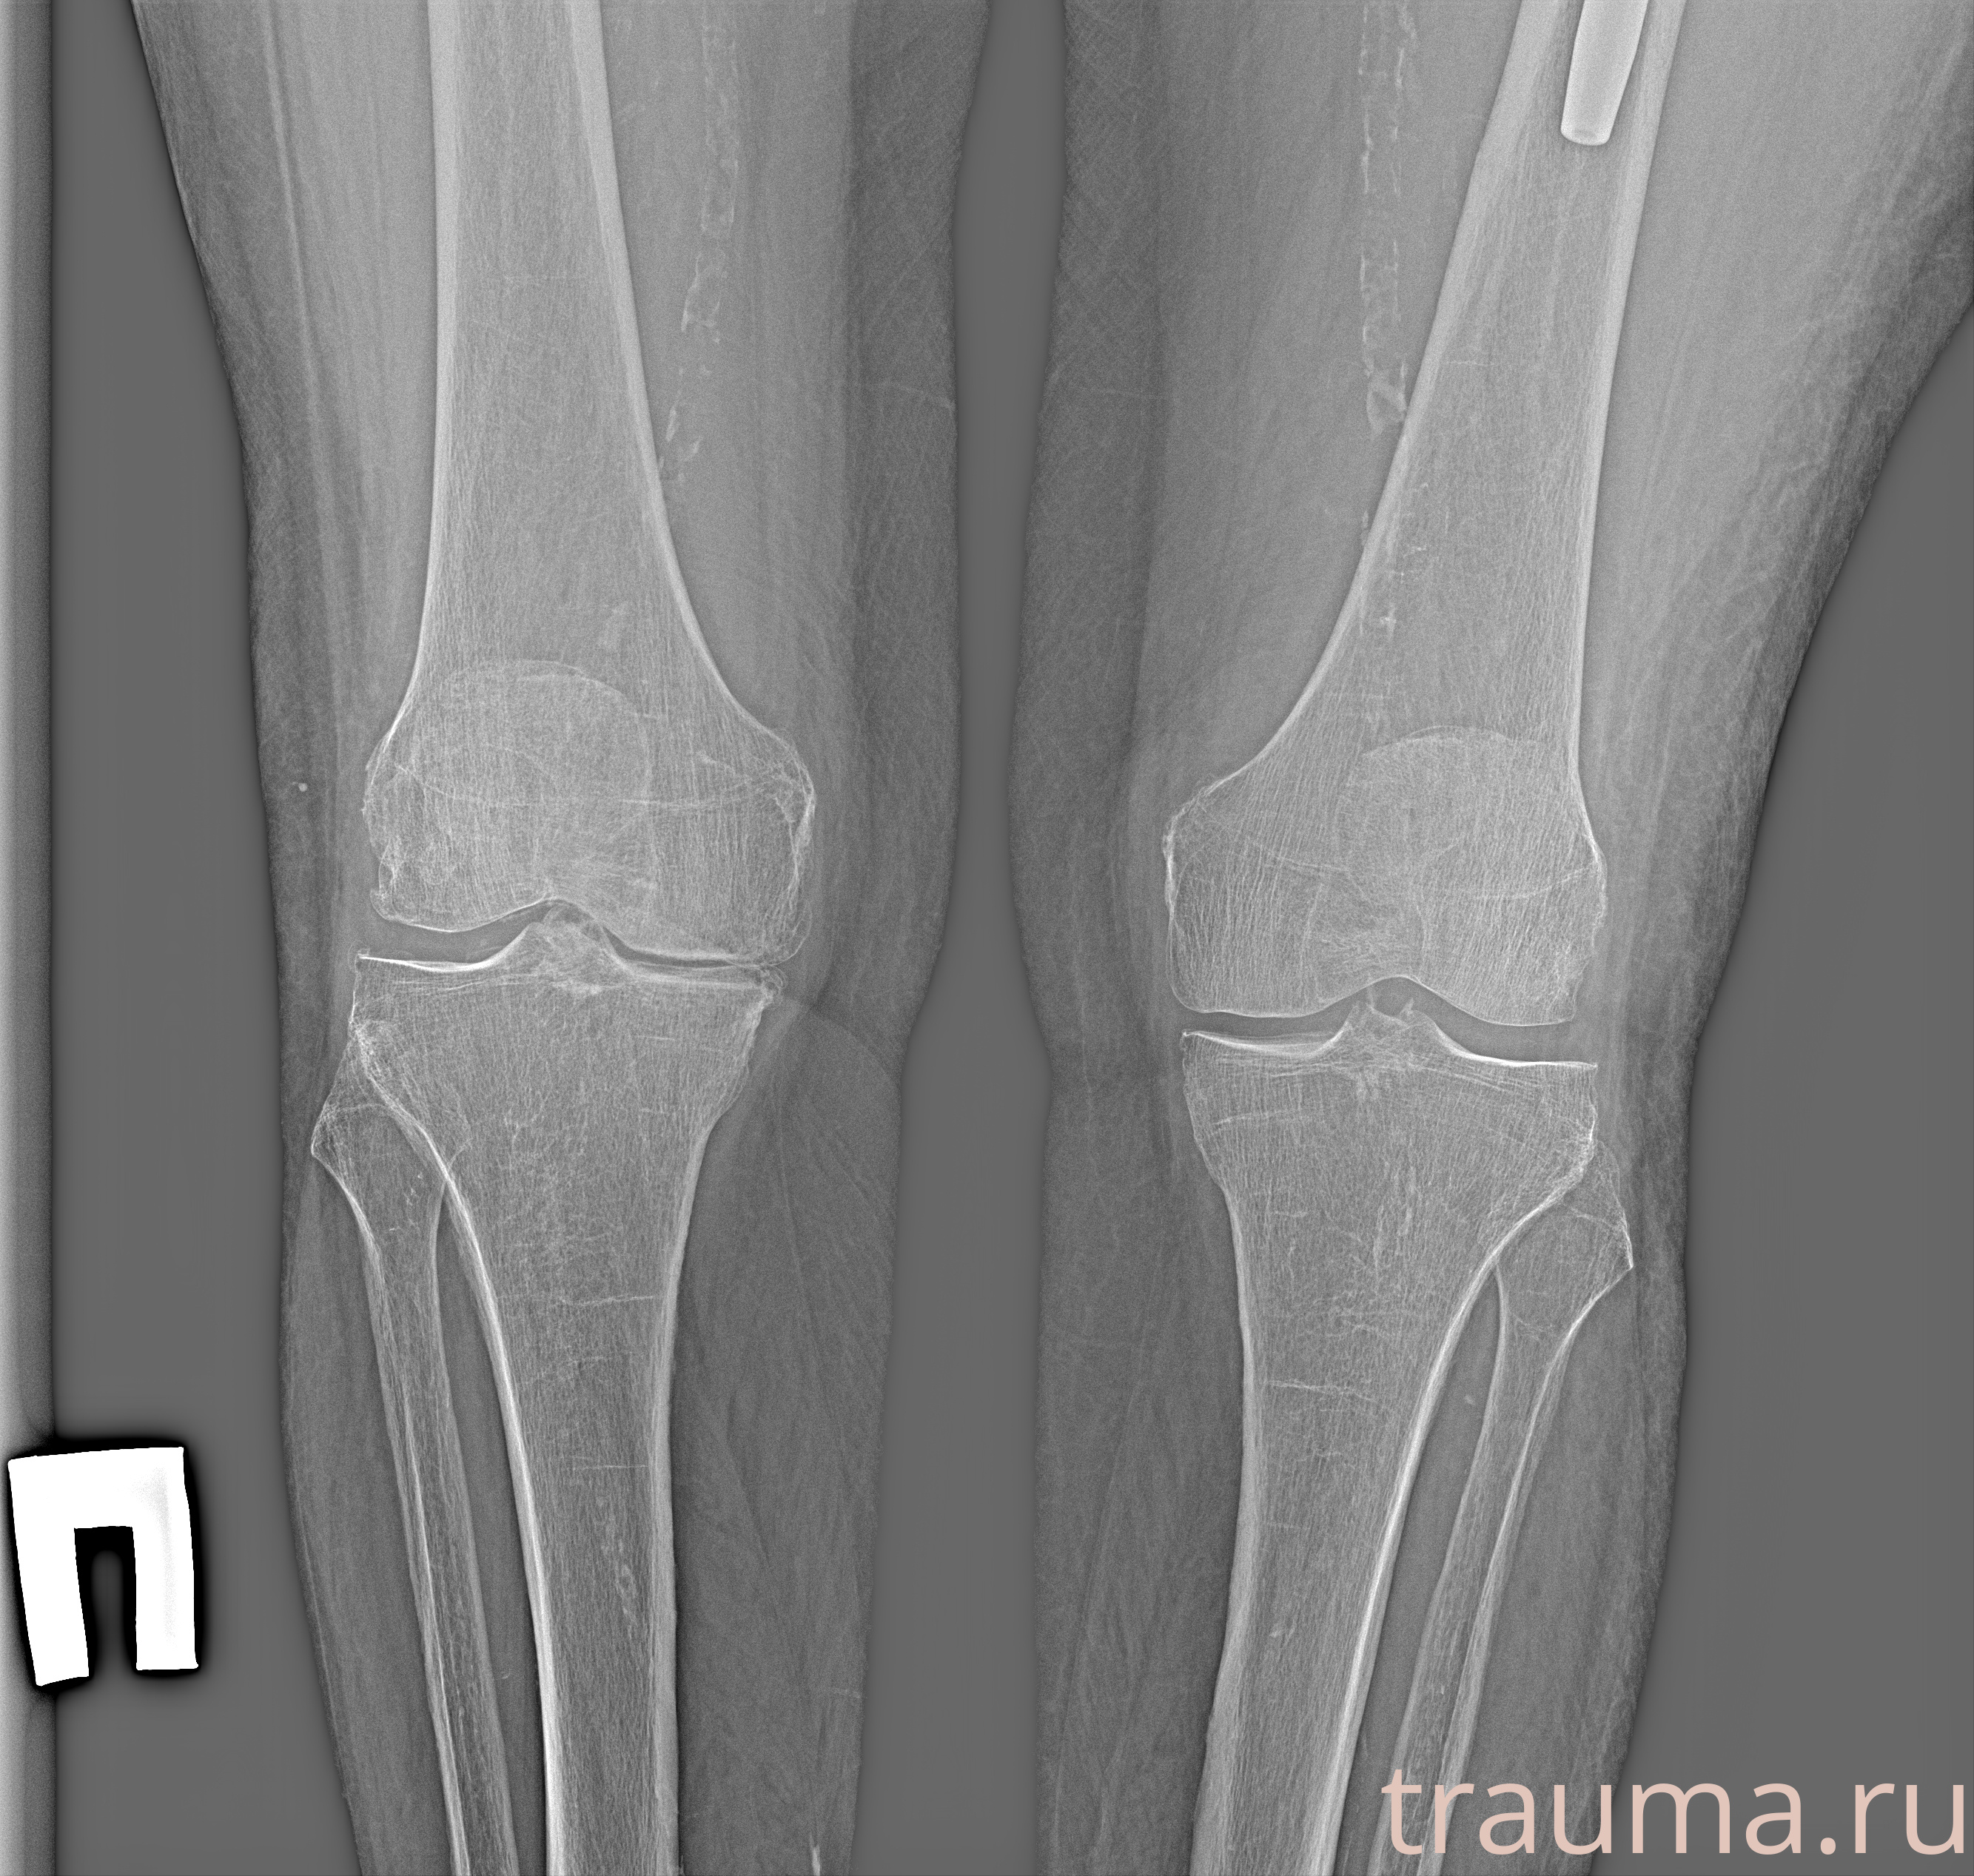

Рентгенограммы